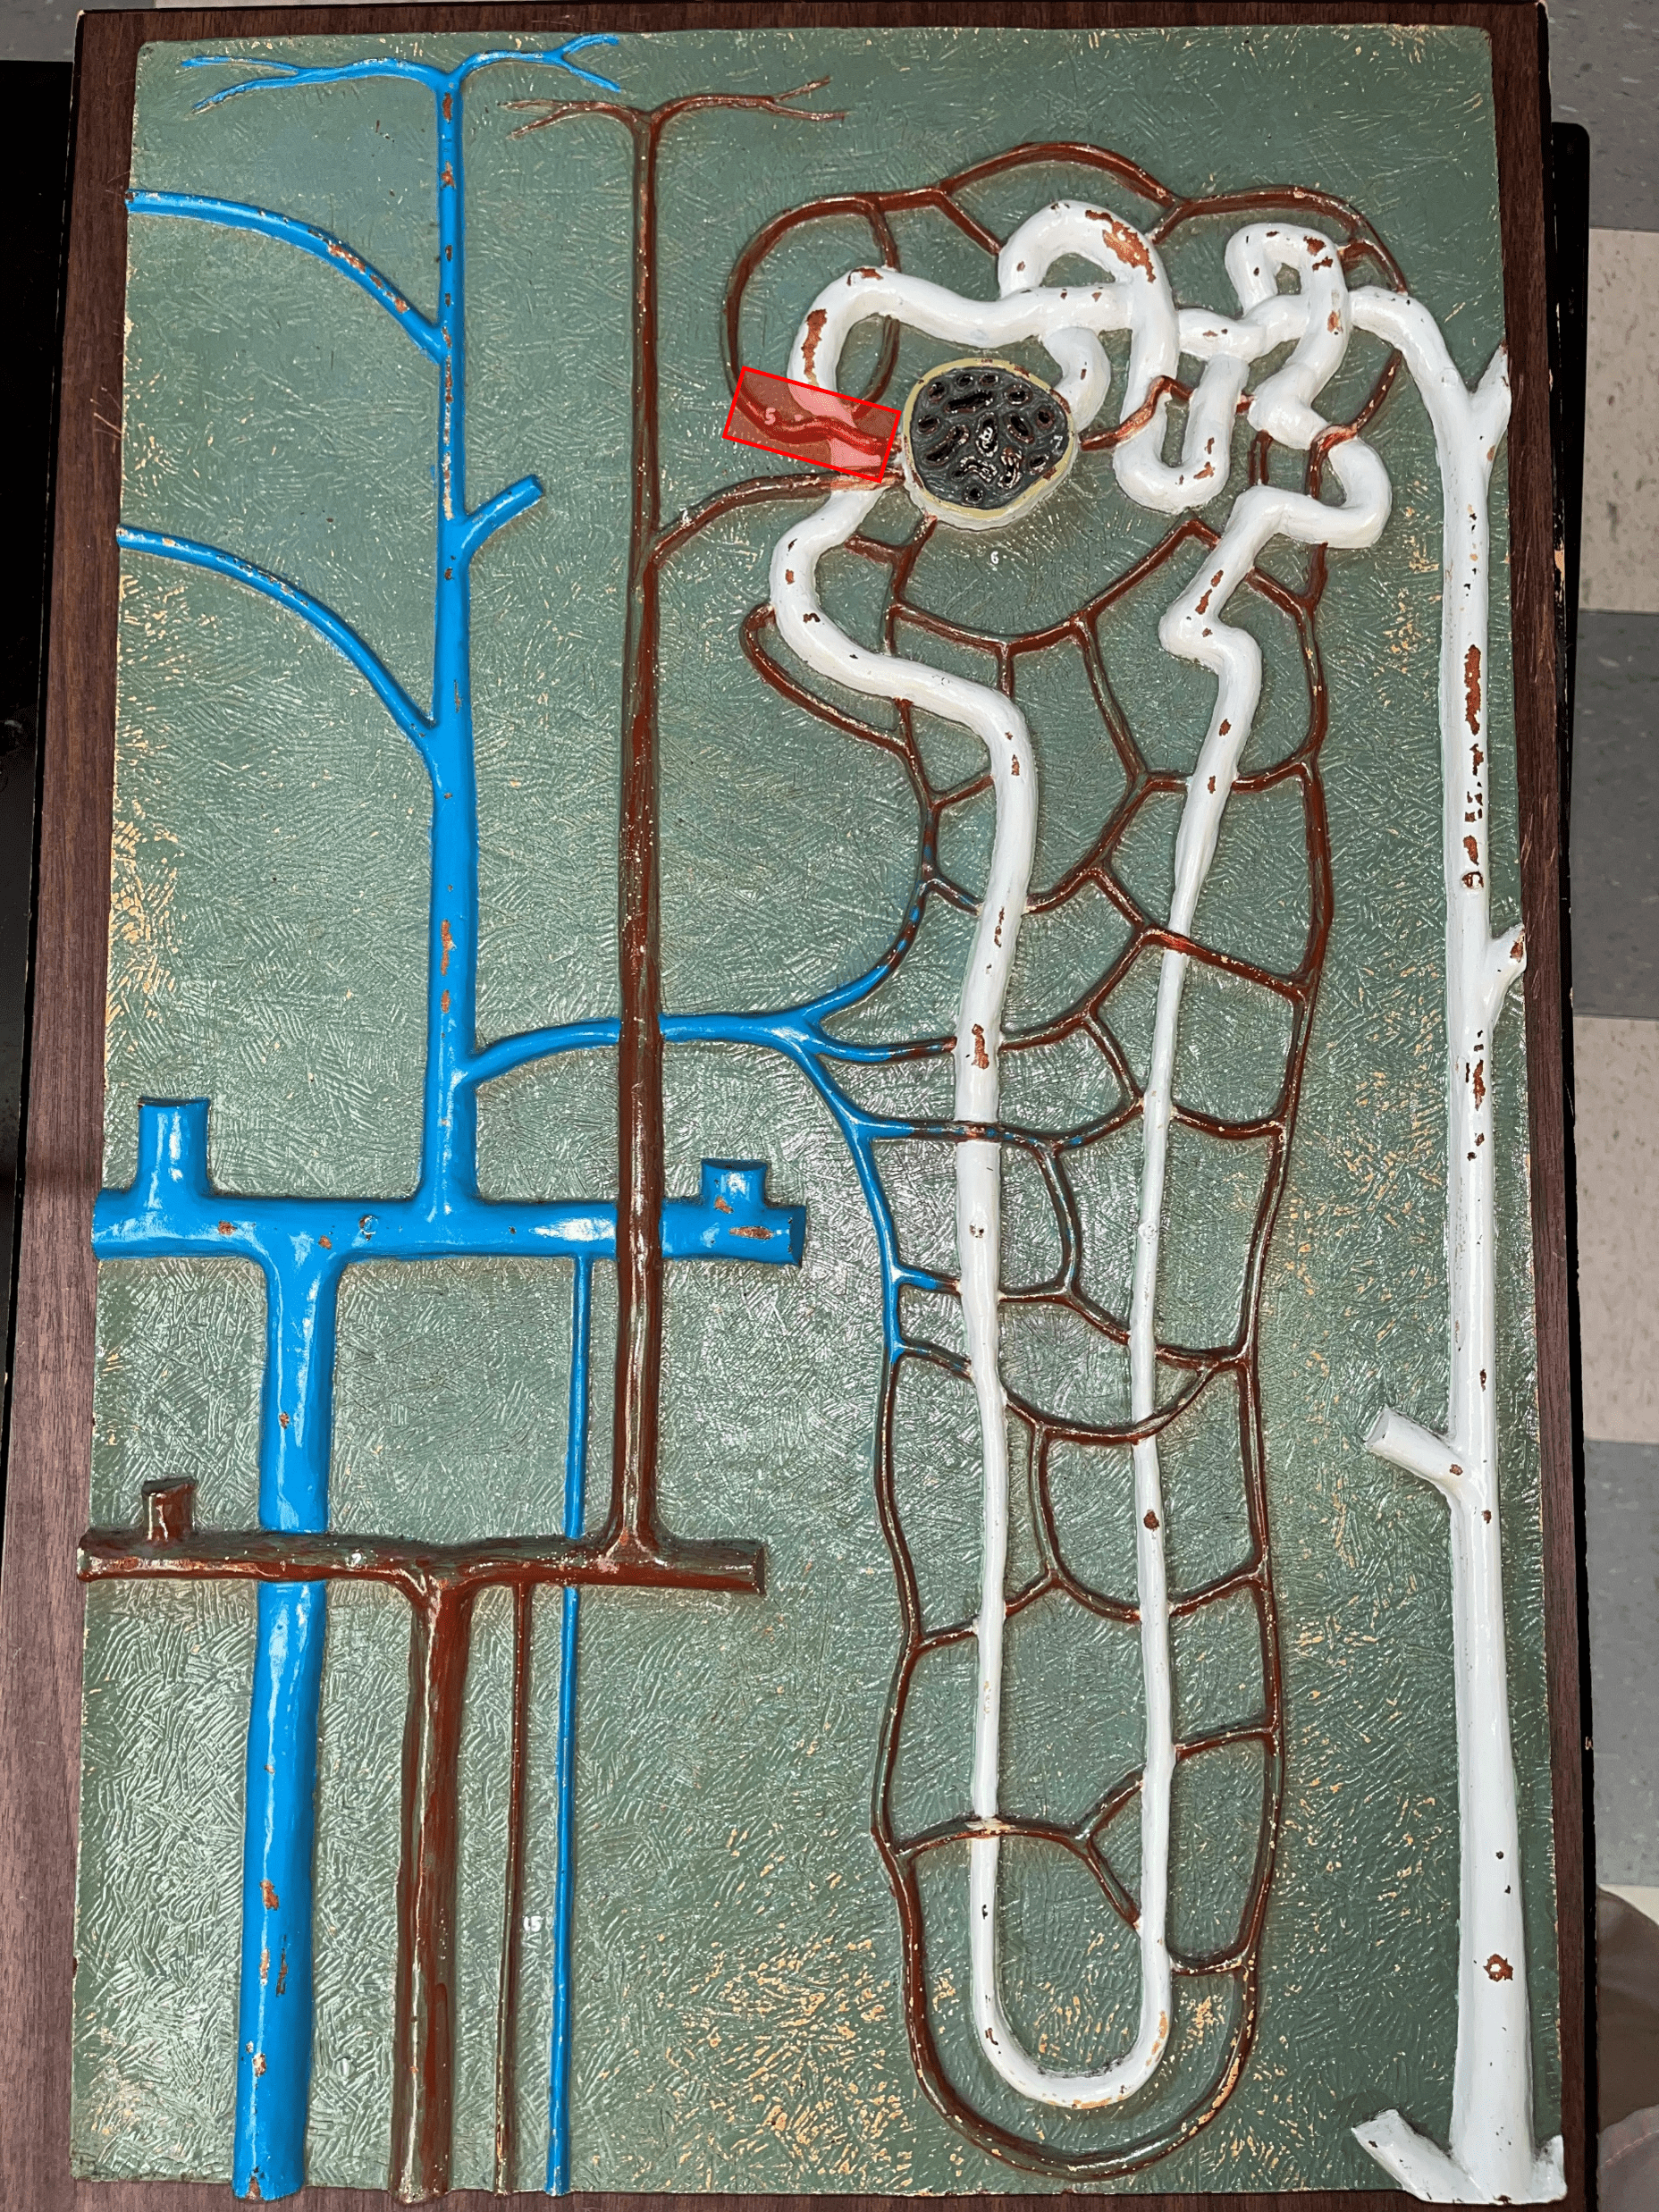

renal corpuscle

• Part of a nephron.

• Filters blood.

• Composed of a glomerulus enclosed within a glomerular capsule.

• Filters blood.

• Composed of a glomerulus enclosed within a glomerular capsule.

41

glomerulus

• Slide histology of the nephron.

• Part of a renal corpuscle.

• The capillary network of a renal corpuscle.

• Part of a renal corpuscle.

• The capillary network of a renal corpuscle.

42

capsular space

• Slide histology of the nephron.

• Part of a renal corpuscle.

• The interior of the glomerular capsule.

• Part of a renal corpuscle.

• The interior of the glomerular capsule.

43

glomerular capsule

• Slide histology of the nephron.

• Part of a renal corpuscle.

• A wall enclosing the glomerulus.

• Shown in the image is the parietal layer.

• Part of a renal corpuscle.

• A wall enclosing the glomerulus.

• Shown in the image is the parietal layer.

44

afferent arteriole

• Branches of an interlobular artery.

• Supplies the glomerulus of a nephron for blood filtration.

• Supplies the glomerulus of a nephron for blood filtration.

efferent arteriole

Vessel carrying blood away from the glomerulus to the peritubular capillaries.